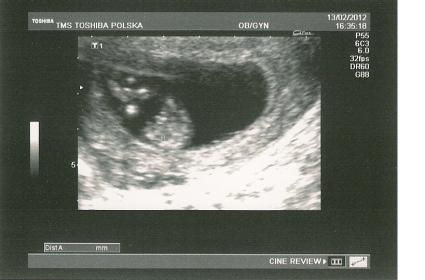

20 weeks Attachment 1883 12 weeks Attachment 1884 12 weeks Attachment 1885